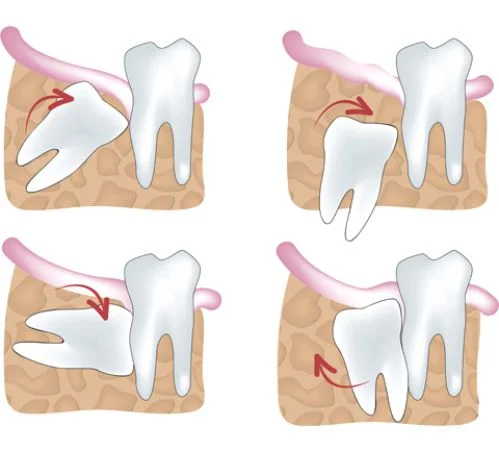

3. CHI PHÍ PHỤC HÌNH RĂNG BỊ TRỒI, XÔ LỆCH

Khi mất răng trong thời gian dài, các răng xung quanh có xu hướng di chuyển vào khoảng trống gây xô lệch, răng đối diện răng mất thì thòng xuống. Việc phục hồi các răng bị trồi, xô lệch này trước khi cấy ghép Implant thường phức tạp và tốn kém hơn so với việc cấy ghép Implant sớm.